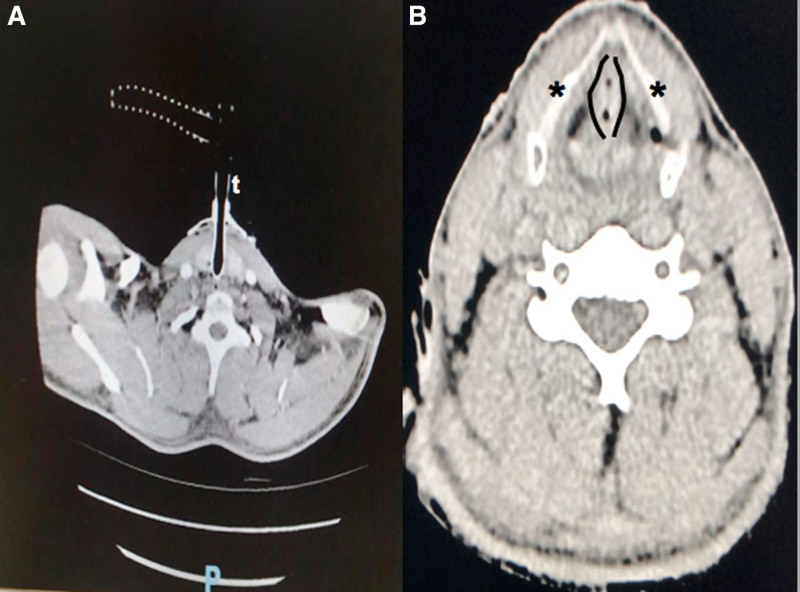

A lightning strike is an extreme event with the highest mortality rate among electrical injuries. Death from a lightning strike is caused by either cardiac arrest or respiratory arrest. It is rare for upper airway damage to occur, but in these cases, airway control is recommended. If transoral intubation is unsuccessful, an emergency cricothyrotomy should be considered. Our case report describes an emergency cricothyroidotomy performed in a harsh environment on a mountain 2300 m above sea level on a patient with extensive burns of his supraglottic structures, after being directly hit by a lightning strike.